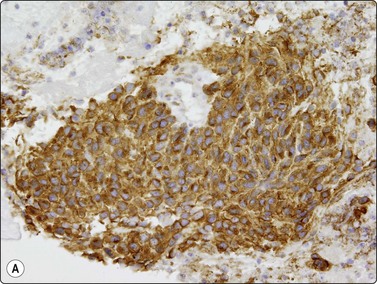

image image

Fig. 11.23 Gastrointestinal stromal tumor (GIST)

(A, B) Cell block sections stained for C-kit (CD117) and CD34 (A, C-kit, HP; B, CD34, HP).

Gastrointestinal stromal tumors (GISTs), formerly classified as smooth muscle tumors, have now been extracted as a distinct entity. They are mesenchymal tumors, arising in the wall of the gastrointestinal tract, showing a spectrum of benign, borderline and malignant behavior. They are typically spindled but there is also an epithelioid variant showing the same antigen profile. Cytodiagnosis of the spindle-celled variant is relatively simple, showing fascicles of spindled cells with elongated, cigar- or comma-shaped nuclei, often set in a wispy filamentous background (Fig. 11.22A and B). The epithelioid variant presents greater difficulty, resembling epithelial tumors. The cells are round, cytoplasm distinct with a perinuclear halo, and nuclei vesicular (Fig. 11.22C). The tumors express CD117 (C-kit) and CD34 (Figs 11.23 and 11.24), but are negative for desmin, S-100 and keratin. Cytopathologists must be ‘GIST-conscious’ owing to the responsiveness of these tumors to Gleevec, which can induce tumor regression and long-term response, even in metastases.132-136